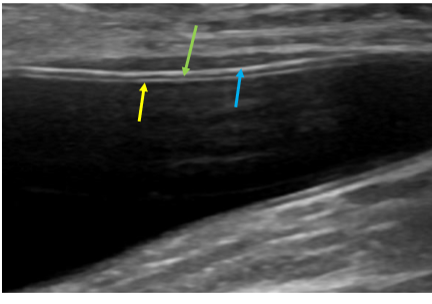

Q

Label the layers of the bladder walls